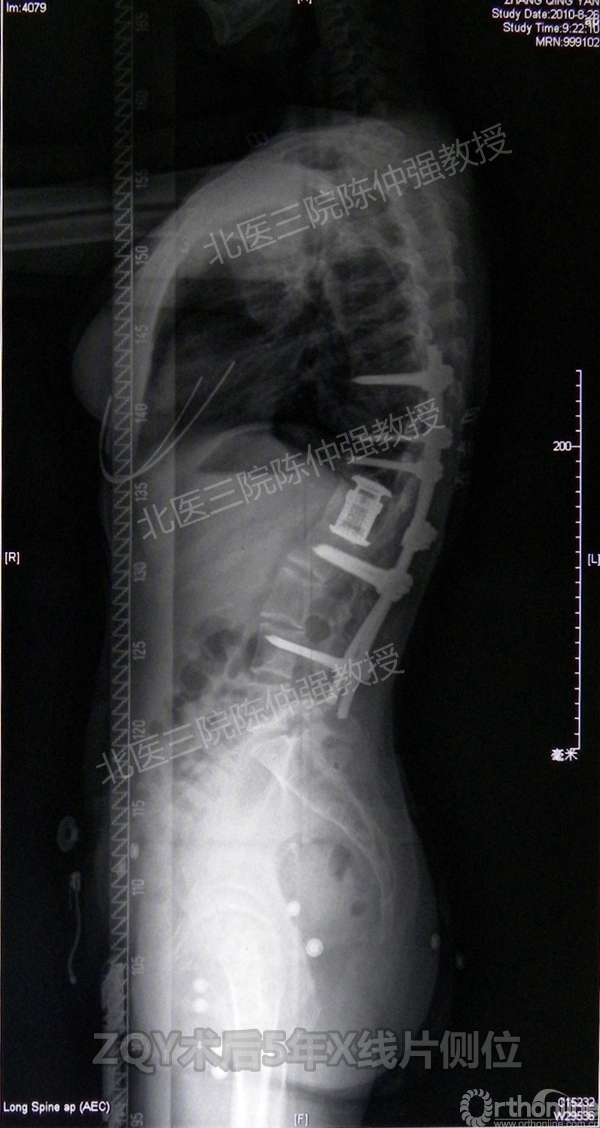

ZQY术后5年

患者女性17岁,胸腰椎陈旧结核性侧后凸畸形,局部呈“麻花状”扭转,无神经功能受损表现。2005年,陈仲强教授带领团队实施后路+侧前方联合入路脊柱节段切除、双轴旋转矫形术。术后患者外观显著改善,神经功能正常。术后随访证实患者截骨矫形节段骨性融合良好,矫形效果持续良好。